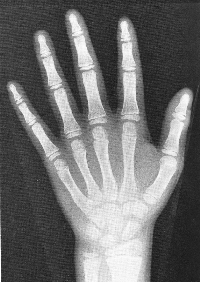

思春期の身長スパートは男女とも女性ホルモン(エストロゲン)に依存しています。エストロゲンは下垂体の成長ホルモン放出ホルモン受容体の感受性を増加させ、成長ホルモン分泌を増加させ、身長発育を促進させます。同時に、エストロゲンにより骨成熟が進行し、最終的には骨端線が閉鎖し、身長発育を停止させます。例えば、男児においてエストロゲン分泌が認められない病態では、男性ホルモン分泌は保たれていますが、骨成熟は進行せず骨端の閉鎖は起こりません。したがって、エストロゲンの骨成熟に果たす役割は明確です。女児の方が身長発育が早く、思春期獲得身長が小さいことは、女児の方がエストロゲンの産生量がより多く、骨成熟がより促進する為です。

思春期のスパート開始後、成人身長に達するまでの獲得身長は、思春期発来年齢が若いほど大きく、年長になるほど小さくなります。平均的な身長の小児では、身長スパート開始年齢を女児で9.5歳、男児で11歳とすると、その後の獲得身長は女児25cm、男児30cmです。